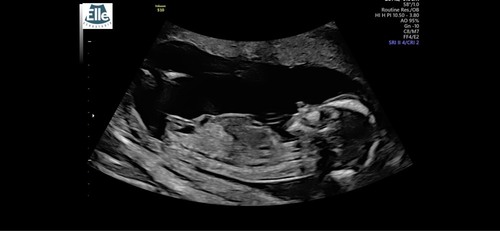

Toch even dubbelchecken… wat zien jullie hier?

Meisje

Goed om te lezen dat jullie hetzelfde zien 😍🩷